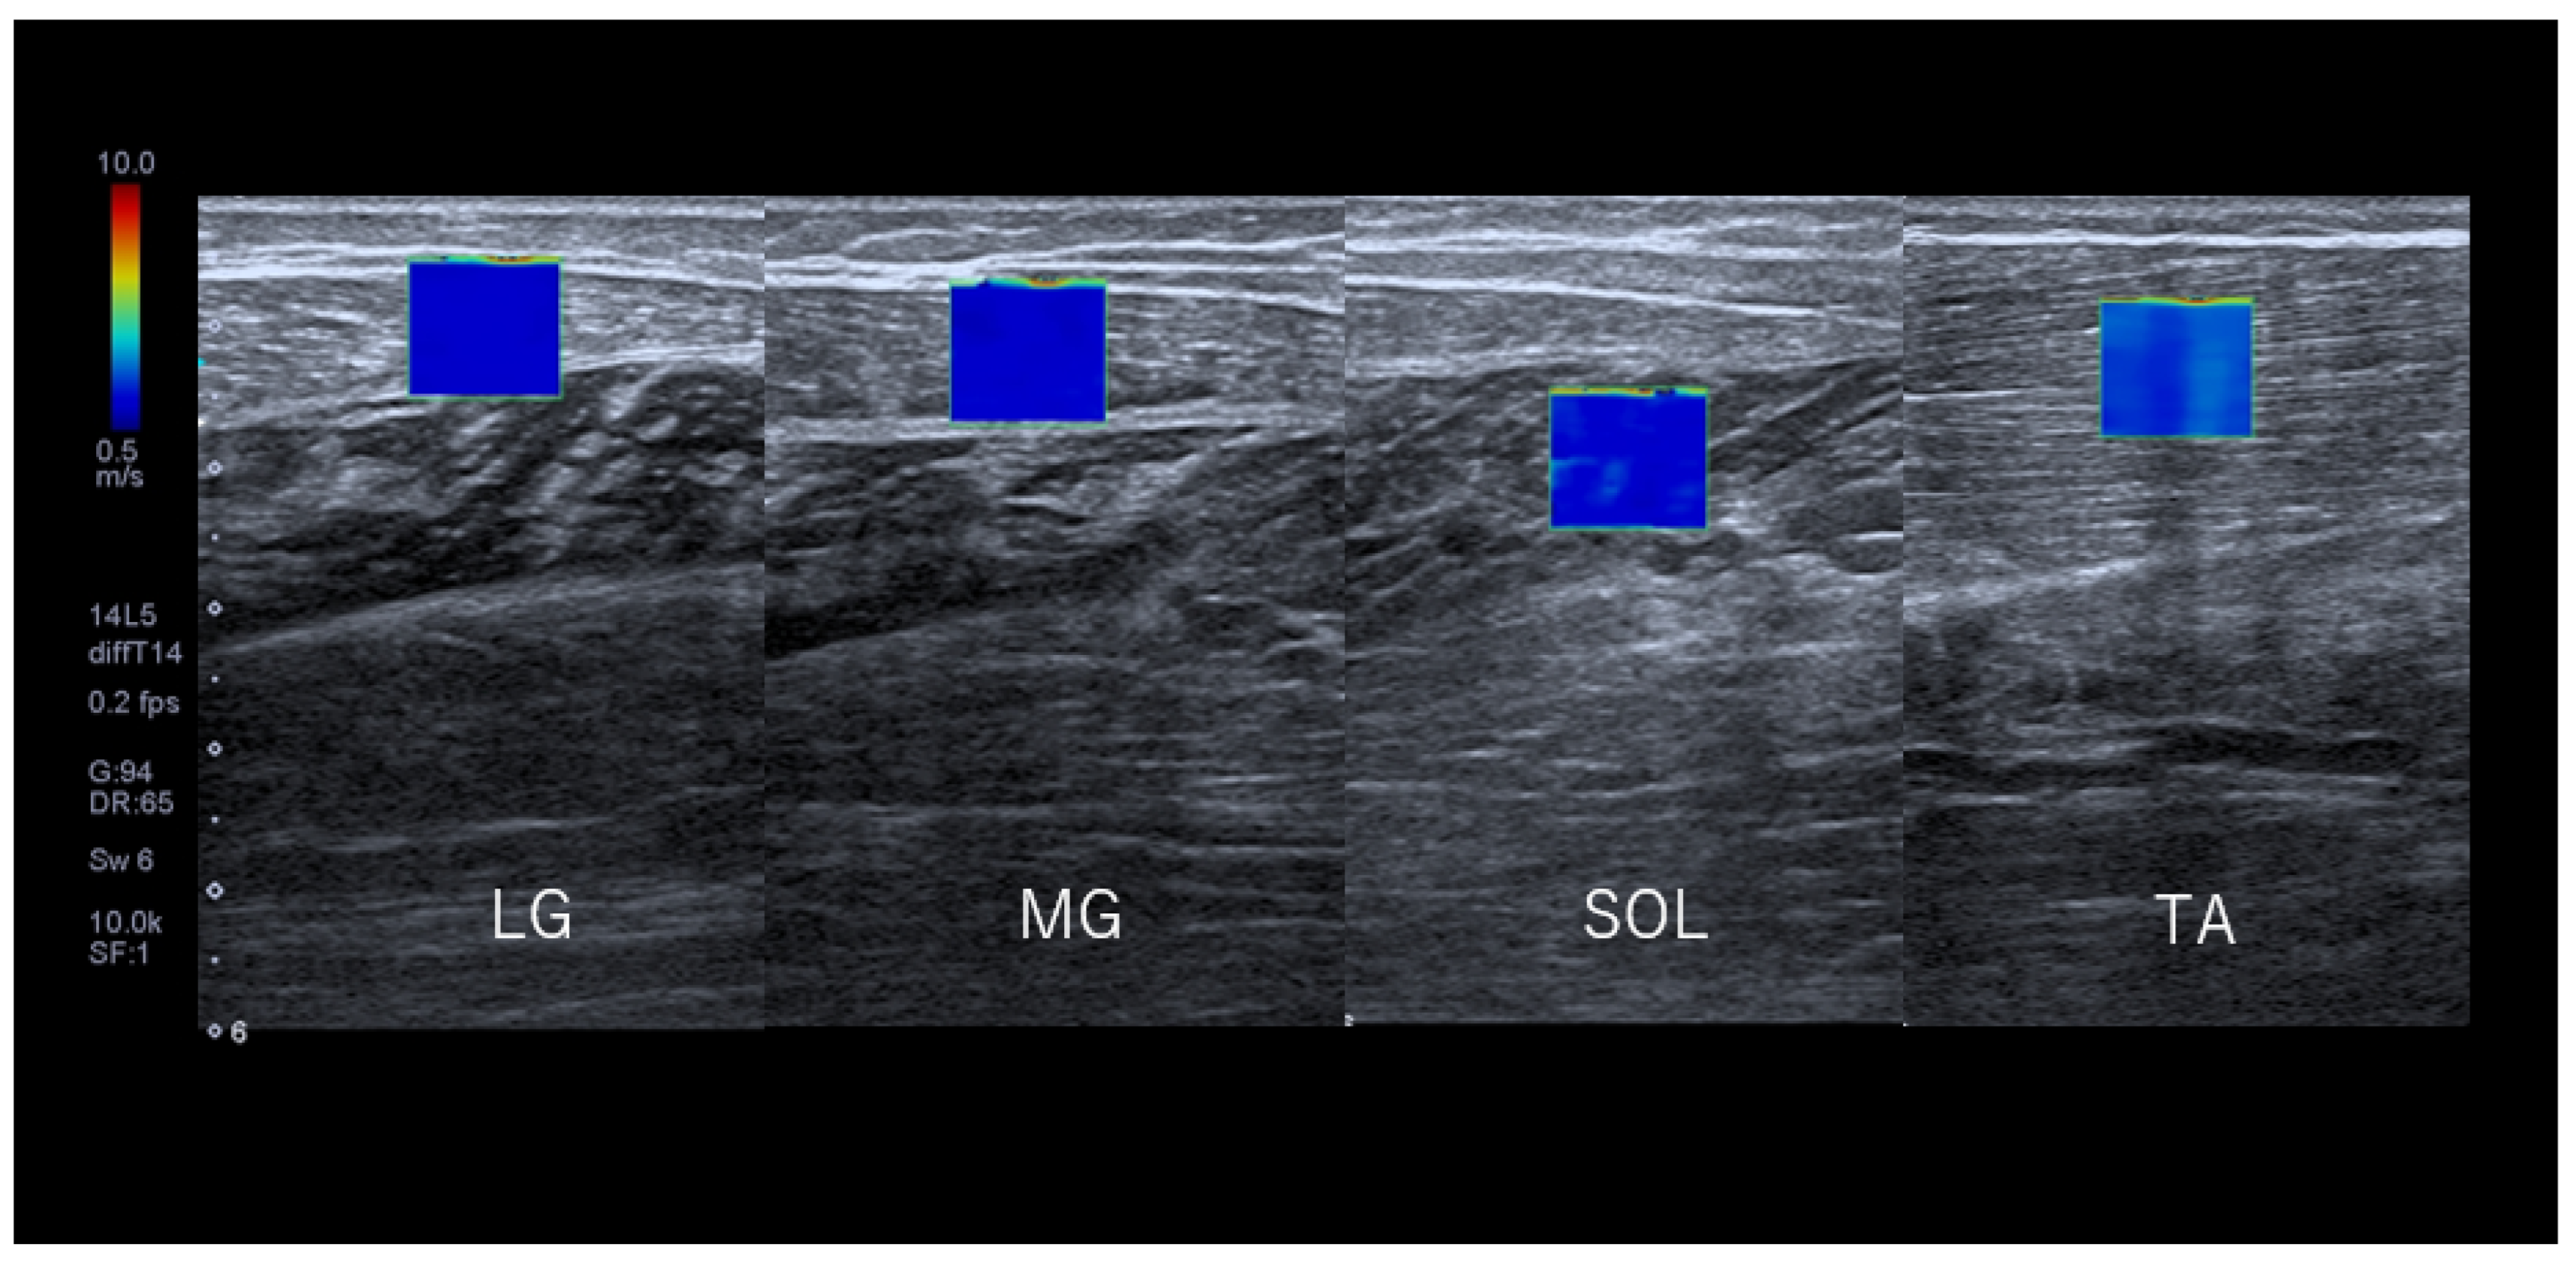

2.4. Measurement of SWV

2.6. SWV Measurements